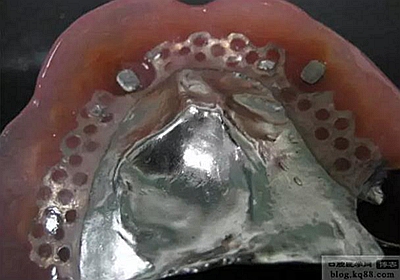

樁制作完成后的模型,磁固位體的銜鐵部分被包埋在根樁的核部位。

將根樁粘到左上3、右上3根內(nèi),然后將磁固位體的磁鐵放到樁的銜鐵上,吸住。

上.下頜分別取模,可以看到上頜模型軟組織包塊周邊與鼻道相通縫隙的印記,同時(shí)還可以看到前庭部分也有與鼻道相通的印記。

在上頜基托放置磁鐵的窩洞內(nèi)打洞.(樹脂排溢孔),將磁體放置到根樁銜鐵上,基托內(nèi)的窩洞內(nèi)放置自凝樹脂,然后將義齒戴入口內(nèi),待樹脂凝固后取下義齒,將多余樹脂打磨掉即可。